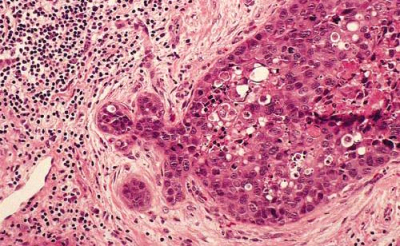

- Medullary carcinoma: שכיחה בכ-5% מכלל סרטני השד. שכיחה יותר בקרב חולות צעירות. מאופיינת ע"י שדות של תאי גידול עם גרעינים בעלי דיפרנציאציה נמוכה, תסנין לימפוציטרי, תאי פלזמה, מוגבל היטב ולרוב לא רואים בסמיכות DCIS. לרוב הקולטנים שליליים והיא מצויה אצל נשאיות BRCA1. היא נוטה פחות להתפשט מה-IDC ובעלת פרוגנוזה טובה יותר (תמונה 35.12)